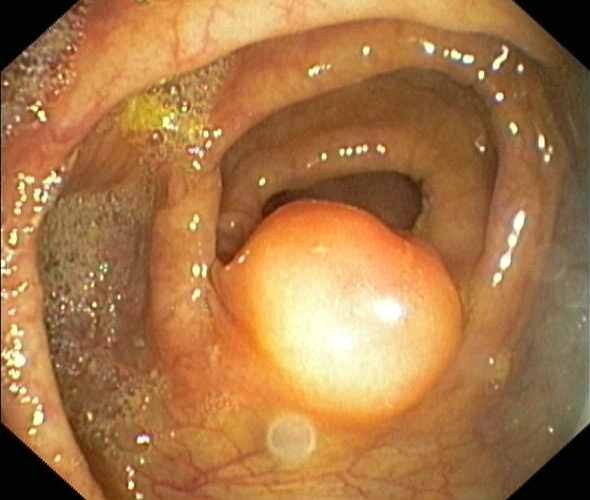

Ileocaecal valve